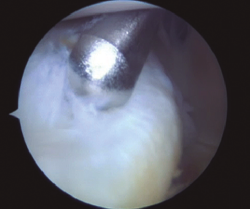

Este tipo de lesiones se pueden clasificar en 5 tipos(5)(Figura 1):

- Tipo 1: lesión de la rampa posterior.

- Tipo 2: lesiones parciales superiores.

- Tipo 3: lesiones parciales inferiores u ocultas.

- Tipo 4: lesiones completas.

- Tipo 5: lesiones dobles.

Figura 1. Visión a través del intercóndilo de lesión inferior oculta, que se detecta con la palpación a través del portal posteromedial.